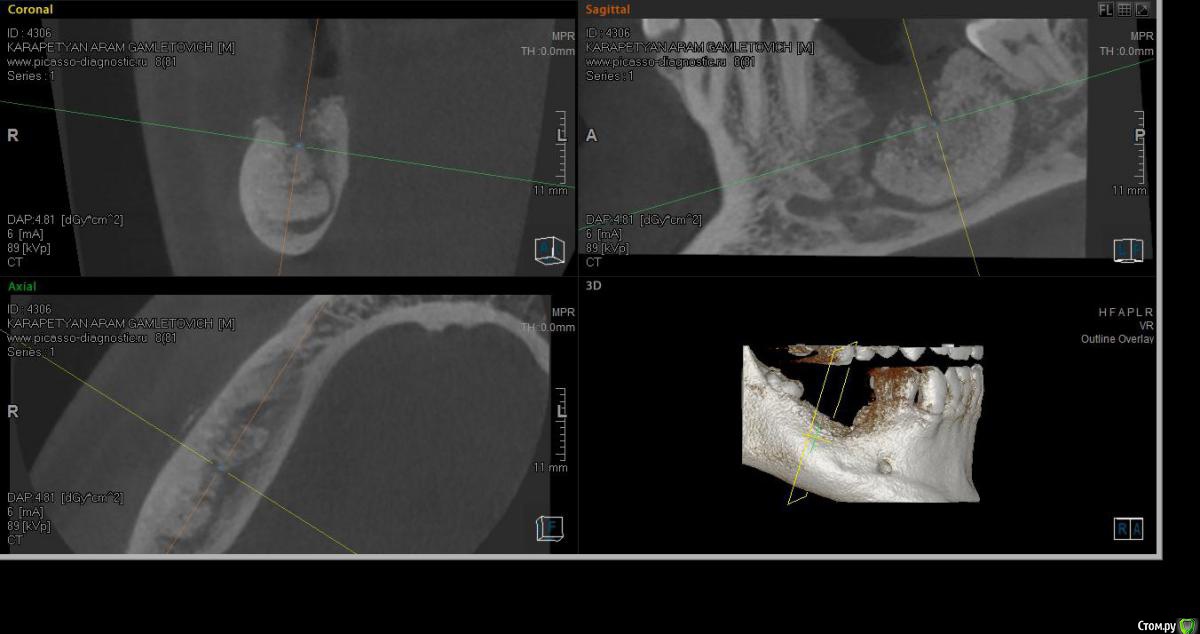

SashaDoc Опубликовано 14 сентября, 2015 Поделиться Опубликовано 14 сентября, 2015 (изменено) Коллеги, нужен совет. Со слов пациента, около 8 мес назад в Армении ему провели операцию по "удалению кисты" н/ч и "засыпали костный порошок" в объеме 6 гр. При мне пациент достал изо рта секвестр 10*5 мм, который он долгое время ощущал языком; во рту - небольшой (3*3мм) дефект слизистой, без отделяемого, в глубине зияет графт. Ничего не болит и не болело.На свежем кт картина не нравится, вопрос - что делать, куда направить? Пациент несколько в стомат теме и понимает, что что-то идет не так, тем более, что врач ему "обещал, что через пол года там кость будет" Изменено 14 сентября, 2015 пользователем SashaDoc Ссылка на комментарий

major Опубликовано 15 сентября, 2015 Поделиться Опубликовано 15 сентября, 2015 На вид белый, не как прижившийсяКонтаминация есть. Я бы сделал ревизию, убрал графт, может не полностью, если есть сосуды. и ждать. + медикаментозная терапия. Ссылка на комментарий